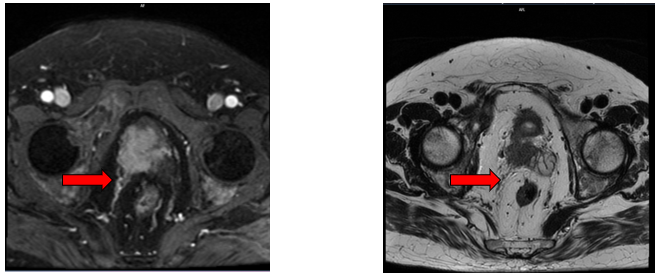

+ Các ổ tổn thương xương cùng, xương chậu, cổ xương đùi 2 bên, hạch cạnh bó mạch chậu bên phải kích thước 31x22mm - Theo dõi thứ phát

Hình 2. Hình ảnh chụp cộng hưởng từ tiểu khung: Hạch cạnh bó mạch chậu bên phải kích thước 31x22mm (mũi tên màu đỏ)